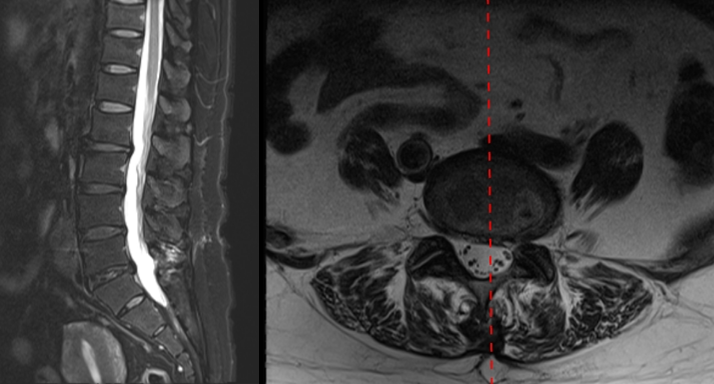

病例

男,64岁。

主诉:腰痛2年、加重伴左下肢疼痛麻木4个月,左小腿后外侧为著。

术后复查